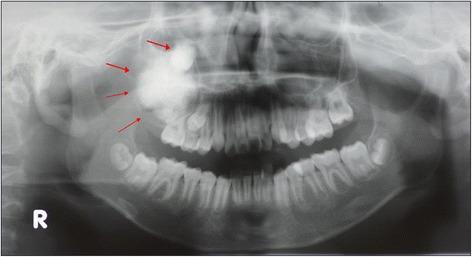

In 2013, an 11-year-old Japanese boy was referred to our department for a painless and large mass of the right maxillary region. A panoramic X-ray showed a unilocular cystic lesion in the right maxilla containing a calcified mass in the lesion associated with an impacted tooth. Computed tomography showed a cystic lesion that included calcified structures and measured 3.6×3.1×2.7 cm. In 2013, the patient underwent tumor extirpation combined with impacted tooth extraction. The histopathological diagnosis was an odontoameloblastoma. No recurrence was noted 27 months after the operation.

2013年,一名11岁日本男孩因右上颌区域无痛性巨大肿物被转诊至我科。全景X线片显示右上颌骨有一单房囊性病变,病变内有一钙化肿物,与一颗阻生牙有关。计算机断层扫描显示一个包含钙化结构的囊性病变,大小为3.6×3.1×2.7厘米。2013年,患者接受了肿瘤切除并拔除了阻生牙。组织病理学诊断为牙源性成釉细胞瘤。术后27个月未发现复发。